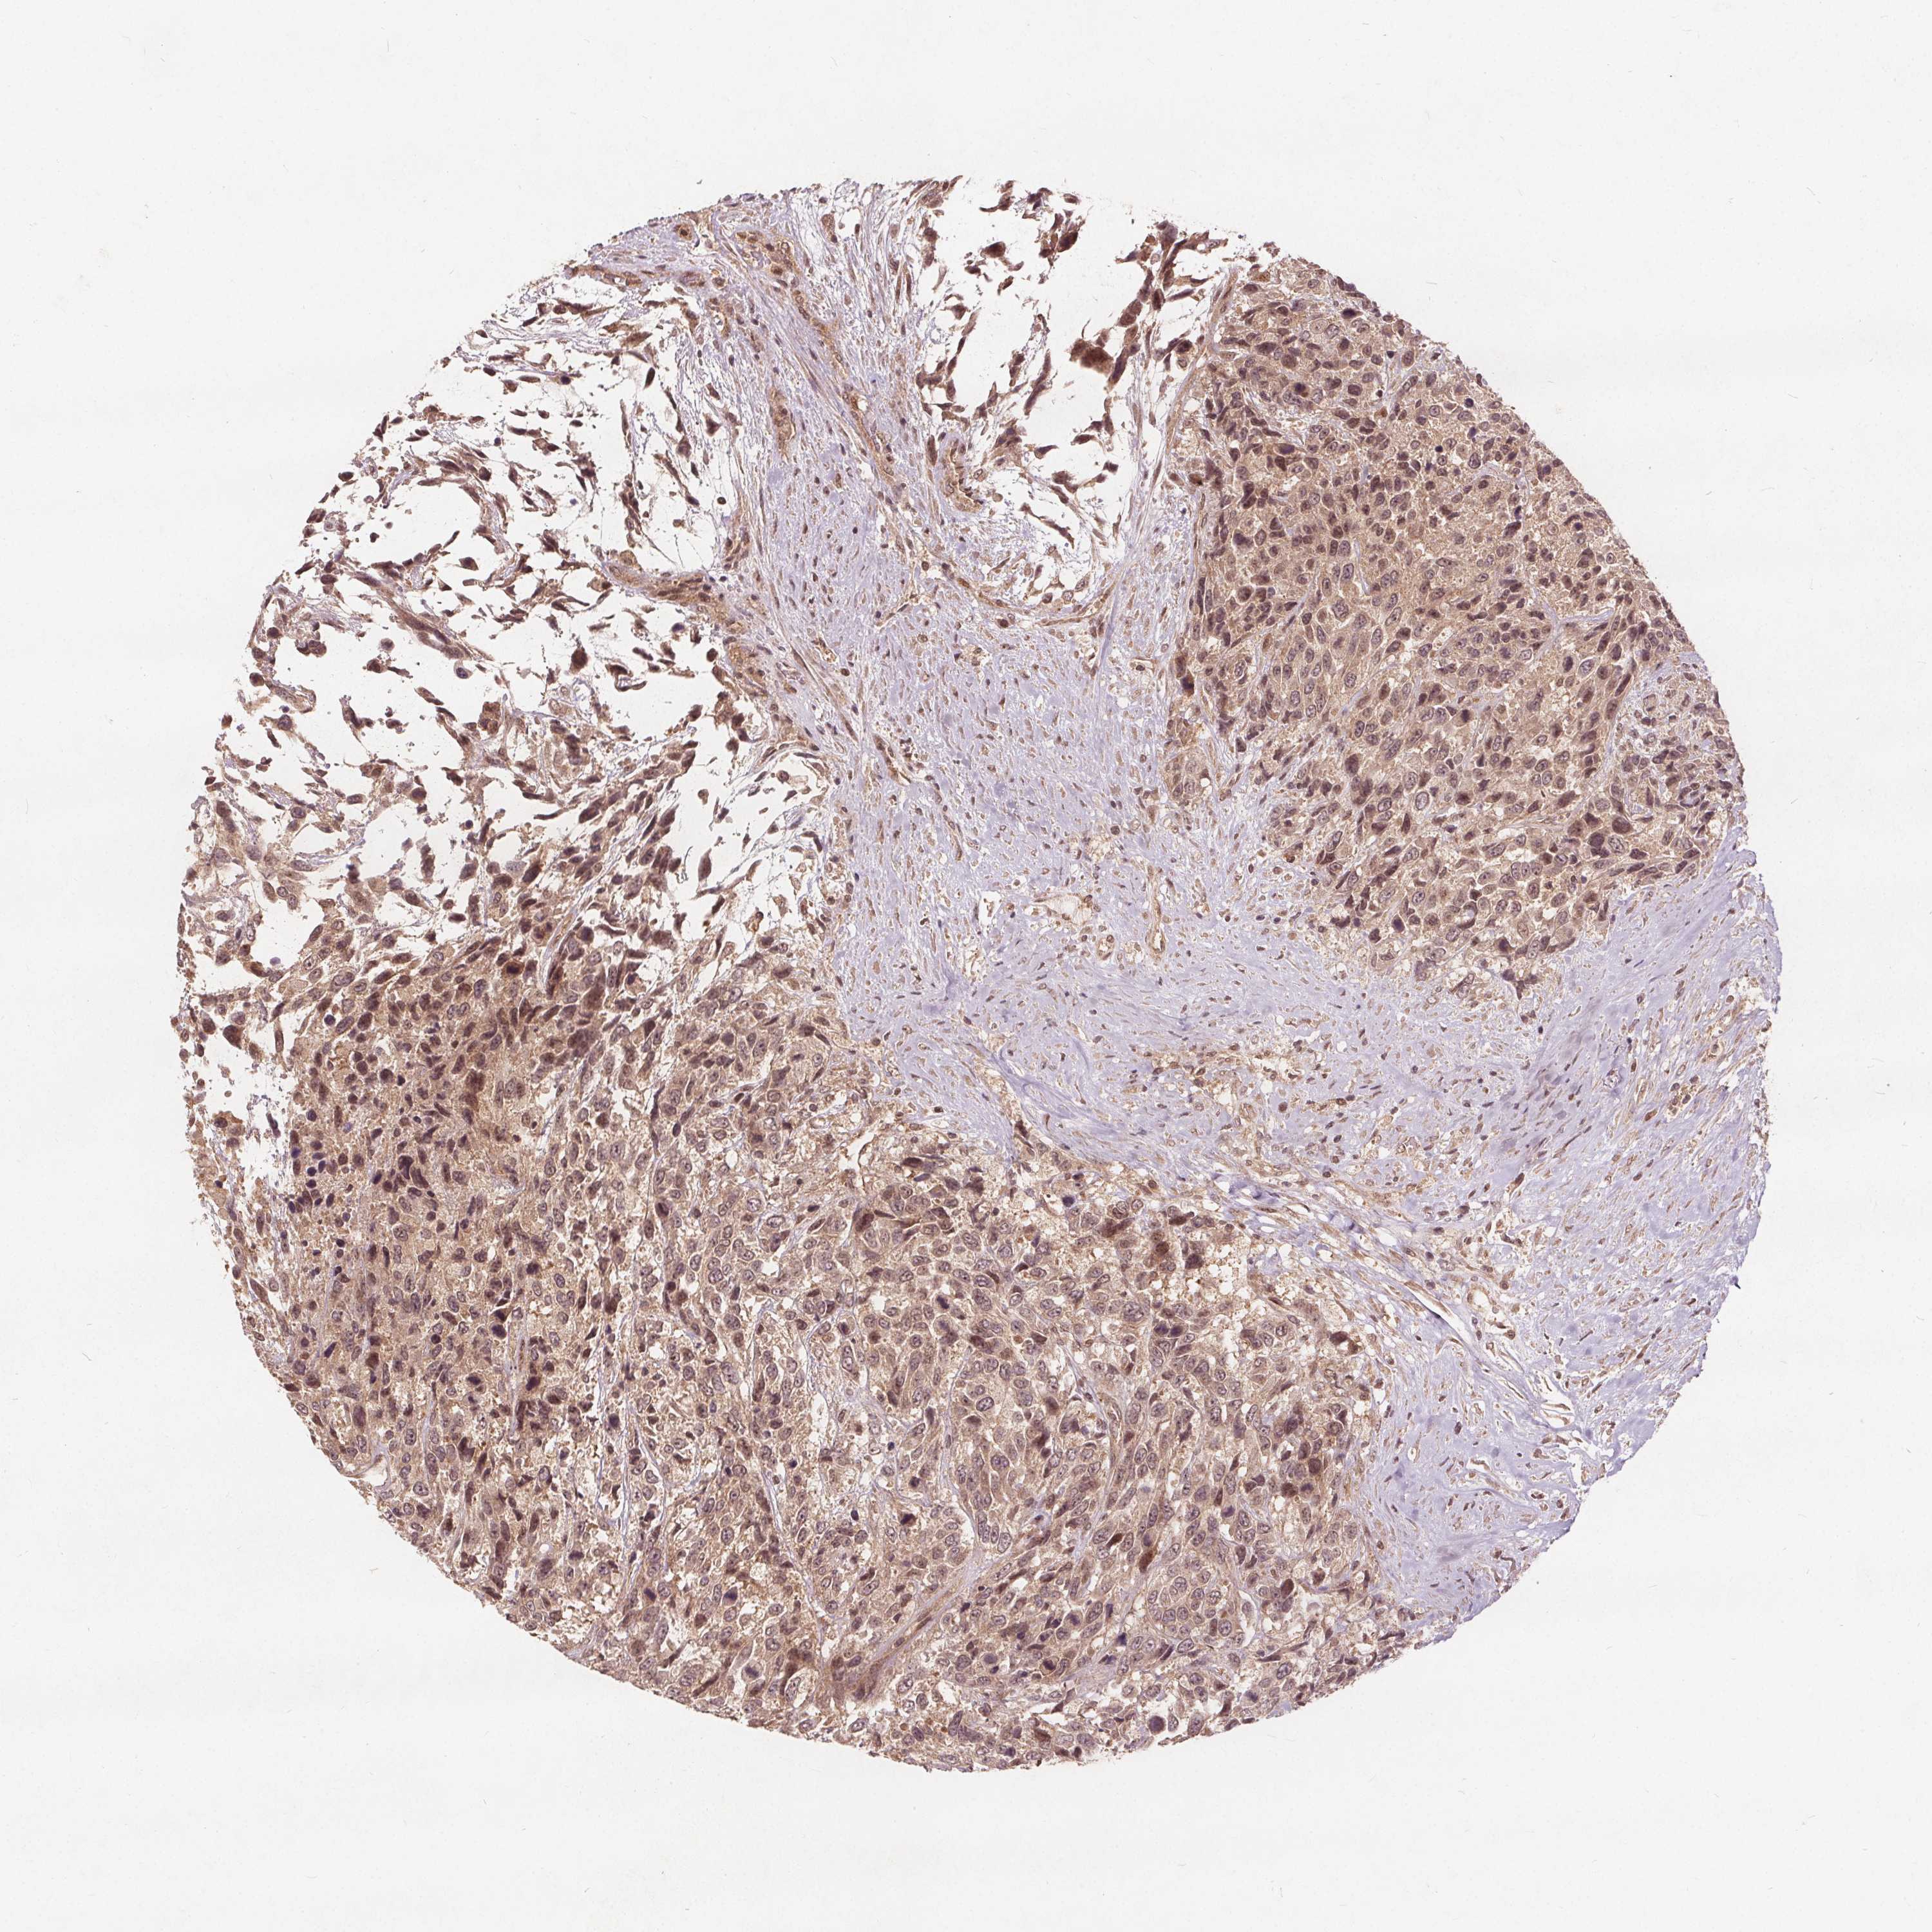

UROTHELIAL CANCER - Protein expressioni

A mouse-over function shows sample information and annotation data. Click on an image to view it in a full screen mode. Samples can be filtered based on level of antibody staining by selecting one or several of the following categories: high, medium, low and not detected. The assay and annotation is described here.

Note that samples used for immunohistochemistry by the Human Protein Atlas do not correspond to samples in the TCGA dataset.

Antibody stainingi

Antibody staining in the annotated cell types in the current human tissue is reported as not detected, low, medium, or high, based on conventional immunohistochemistry profiling in selected tissues. This score is based on the combination of the staining intensity and fraction of stained cells.

Each image is clickable and will lead to virtual microscopy that enables deeper exploration of all samples and also displays staining intensity scores, fraction scores and subcellular localization as well as patient and tissue information for each sample.

Antibody HPA065425

Antibody CAB069426

Staining

High

Medium

Low

Not detected

Intensity

Strong

Moderate

Weak

Negative

Quantity

>75%

75%-25%

<25%

None

Location

Nuclear

Cytoplasmic/membranous

Cytoplasmic/membranous,nuclear

Urothelial carcinoma, High grade

Urothelial carcinoma, NOS

Urothelial carcinoma, Low grade